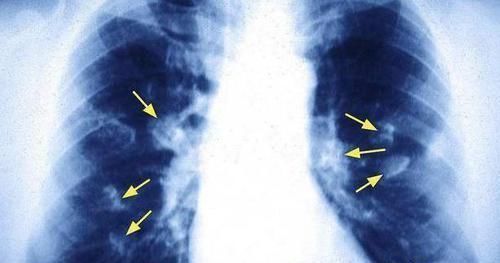

日常生活中,当我们谈到癌症时,它是每一个人都不愿意面对的疾病。无论是任何一种癌症,任由它继续发展下去都很容易会危及生命安全。近些年来,肺癌的发病率也是越来越高,甚至有着不断上升的趋势。其实无论是任何疾病,包括癌症,它们在早期阶段时,也是有信号的,如果你能够及时发现,及时治疗,那么还是有很大希望逆转的,一旦它发展到了中晚期,就有点回天乏术了。当身体出现这5个症状,可能是肺癌早期发出的求救信号,别不当回事!

■肺癌早期也是有迹可循的,身体出现这5个异常,还请及时就诊检查!